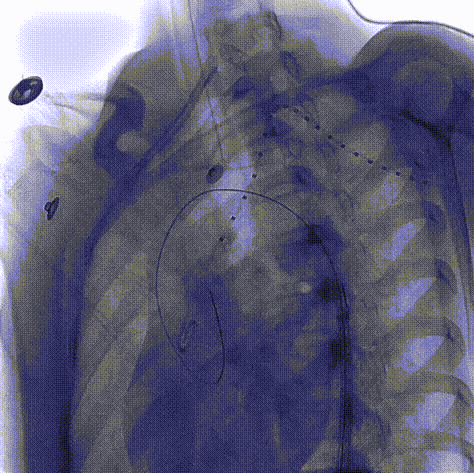

患者女性,15岁,因意外高空坠落收治入院。患者入院后行CTA检查,可见主动脉峡部局限夹层,小弯侧距离左锁骨动脉后缘锚定距离7.9mm,患者年纪小,主动脉直径较细。

术前CTA